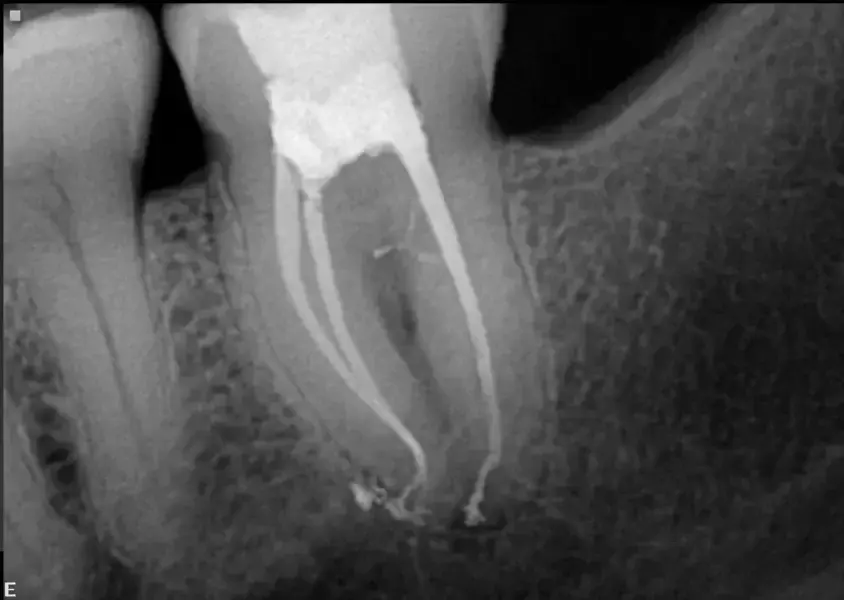

С помощта на този софтуер може да се визуализира триизмерен модел на зъба с проследяване на каналите и приблизителните им размери, което ни дава представа какво може да се очаква (фиг. 4). Например в този случай средната работна дължина беше около 27 мм за този втори горен молар с четири канала и такъв вид анатомия – наричам такива случаи „двойно еспресо“, защото представляват леко предизвикателство. Например дисталният канал имаше остра извивка като върха на кука. Всички тези данни могат да помогнат при избора на пилите, използвани за оформяне и почистване на кореновата канална система, и последователността им. За оформянето на каналите бяха използвани пили Traverse и ZenFlex (Kerr Dental; фиг. 5). В дисталния корен пилата 30/.04 не беше използвана в последните 2 мм, за да се избегне неправилно оформяне на тази област. Промиването на канала беше извършено в съответствие с последователността на промиване на Sleiman (публикувана в списание roots 1/2014 г.). Триизмерната обтурация на каналите беше извършена със система за обтурация elements IC (Kerr Dental; фиг. 6). Обтурирането беше завършено, а незабавните следоперативни рентгенографии показаха, че всички канали са запълнени и запечатани (фиг. 7а–с).

Фиг. 7а Рентгенографии, направени моментално след обтурирането на каналите, показващи 3D запълване на кореновата система под различен ъгъл.

Фиг. 7б Рентгенографии, направени моментално след обтурацията на каналите, показващи 3D запълване на кореновата система под различен ъгъл.

Фиг. 7в Рентгенографии, направени моментално след обтурацията на каналите, показващи 3D запълване на кореновата система под различен ъгъл.